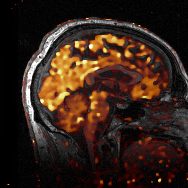

Over the last decades, the total variation (TV) evolved to one of the most broadly-used regularisation functionals for inverse problems, in particular for imaging applications. When first introduced as a regulariser, higher-order generalisations of TV were soon proposed and studied with increasing interest, which led to a variety of different approaches being available today. We review several of these approaches, discussing aspects ranging from functional-analytic foundations to regularisation theory for linear inverse problems in Banach space, and provide a unified framework concerning well-posedness and convergence for vanishing noise level for respective Tikhonov regularisation. This includes general higher orders of TV, additive and infimal-convolution multi-order total variation, total generalised variation (TGV), and beyond. Further, numerical optimisation algorithms are developed and discussed that are suitable for solving the Tikhonov minimisation problem for all presented models. Focus is laid in particular on covering the whole pipeline starting at the discretisation of the problem and ending at concrete, implementable iterative procedures. A major part of this review is finally concerned with presenting examples and applications where higher-order TV approaches turned out to be beneficial. These applications range from classical inverse problems in imaging such as denoising, deconvolution, compressed sensing, optical-flow estimation and decompression, to image reconstruction in medical imaging and beyond, including magnetic resonance imaging (MRI), computed tomography (CT), magnetic-resonance positron emission tomography (MR-PET), and electron tomography.